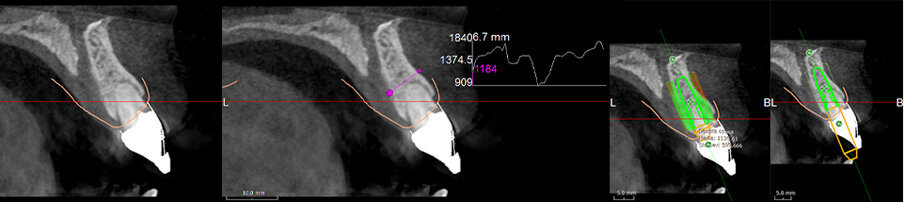

It became evident that the short-rooted tooth could be extracted without compromising the buccal bone, and that there was sufficient bone volume and quality to obtain good primary stability of the implant. Thanks to the AIS 3D App software, this information can be visualised using the bone density tool and linear measures tool (Fig. 10c) and represented in a graphic or according to a coloured scale. The presence of the nasopalatine duct prohibited ideal palatal positioning of the implant, and if the implant were to be placed flush with the palatal alveolar bone, this would have resulted in a 1.5–2.0 mm high exposure of the implant collar on the buccal aspect (Fig. 11b). This information, combined with the aesthetic analysis, led to the decision to place the implant in that position and to augment the buccal bone volume with a contemporaneous GBR procedure, thus also providing for major soft tissue support. As often described in the literature, it is to be expected that in some measure the implant will deviate buccally2–4 from the original planning because of the major mechanical resistance of the palatal plate. The author’s team prefers whenever possible screw-retained solutions. Several production centres are capable of milling angulated screw access holes in cobalt-chromium abutments of up to 25°,5 which is a range that covers most cases in daily practice. It can be easily checked in the implant planning software whether the future access hole will exit on the palatal aspect of the tooth, either by angulating the implant extension tool or by choosing a virtual abutment from the library. Confirming being in the safety range from this point of view allowed for an approach that foresaw the implant in native bone without the necessity for major GBR on the apical aspect of the implant. Knowing that a flap needed to be raised to facilitate the marginal tissue augmentation, it was decided to use a surgical guide (Figs. 11c) for only the first drill to determine with precision the position and angulation of the osteotomy that would be performed freehand thereafter. In order to limit surgery time and eliminate unpredictable factors inherent in immediate loading, a removable temporary prosthetic tooth was produced in advance.